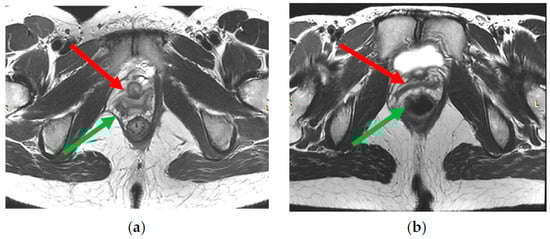

The complex that raises the anus consists of the pubo-rectal, pubo-coccygeal, and iliopsoas-coccygeal muscles. Of these, the pubo-rectal rectus muscle (Figure 1), which branches from the pubic bone in front and covers the anorectal transition forming the urogenital cleft, holds the pelvic floor organs together and adjoins the pubic bones, preventing prolapse of these organs, and also forms the angle between the anal canal and rectum and plays a role in retaining feces [35].

Figure 1. Pubo-rectal muscle U-shaped is highlighted in red, in the form of a loop covers urethra, vagina, and rectum, forming urogenital cleft.

Figure 2. Normal indicators of pelvic organ condition. (a)—anorectal angle at rest, (b)—anorectal angle during bowel obstruction and tension of the puborectalis muscle, (c)—anorectal angle during relaxation of the puborectalis muscle.